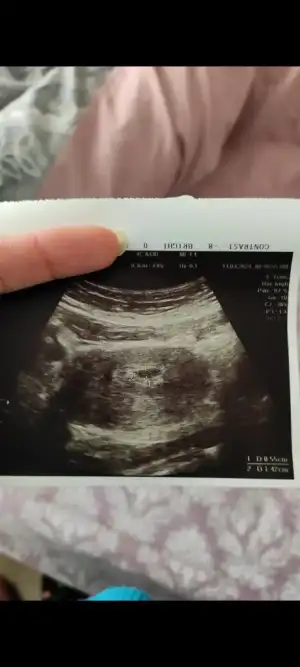

Ay hadi gözünüz aydın ya yarın için heyecanlıyım:)evet keseyi geçen hafta görmüştük bu cumartesi de kalp atışını dinledik . Sanırım o yüzden :)